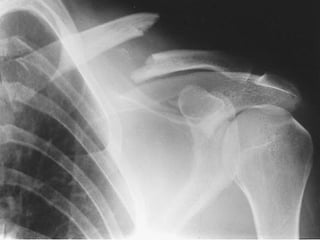

FRACTURA DE CLAVÍCULA:

DEFINICION

Ruptura del hueso de la clavícula.

Pérdida de continuidad de la

clavícula.

DIAGNOSTICO